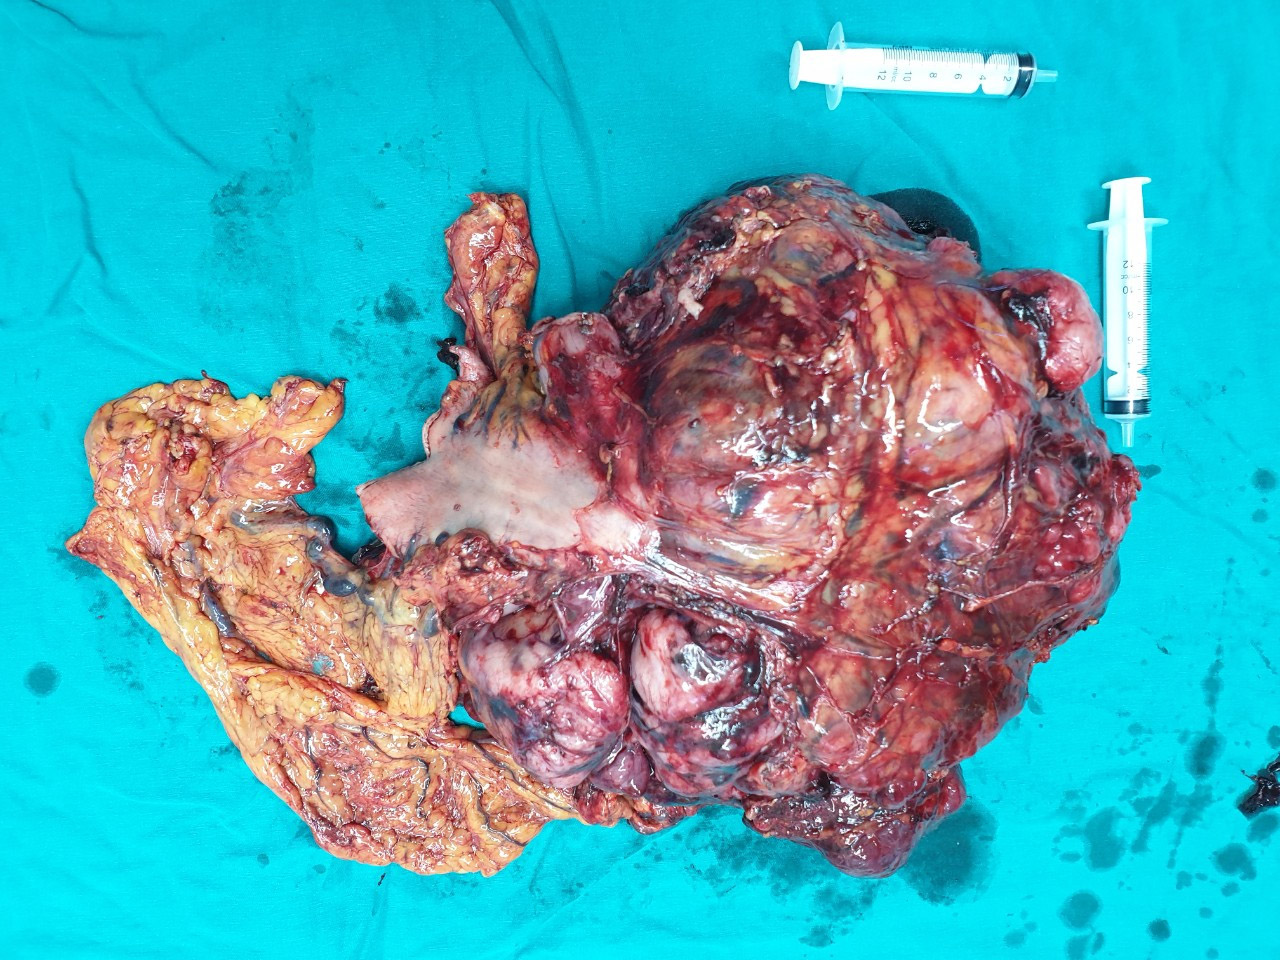

Hình 4: Khối u kích thước tới 30cm

Hình 5: Khối u nặng tới gần 5kg

Tại Bệnh viện Bạch Mai, ông đã được chẩn đoán mắc bệnh GIST dạ dày và được chỉ định phẫu thuật tại Khoa Phẫu thuật Tiêu hóa – Gan mật tụy. Ca mổ được dự kiến là khó khăn, phức tạp thậm chí có thể không làm được gì. Tuy nhiên, dưới sự quyết tâm, nỗ lực của các phẫu thuật viên dày dặn kinh nghiệm và sự phối hợp của các bác sĩ gây mê hồi sức, sau 3 tiếng tập trung cao độ, kíp phẫu thuật đã cắt được khối u khổng lồ đường kính hơn 30 cm, nặng 5 kg cùng gần như toàn bộ dạ dày của ông T mà không làm tổn thương đến các tạng xung quanh.

Trường hợp thứ 2: Bệnh nhân N.Q.T, 62 tuổi, có tiền sử viêm dạ dày hơn 10 năm điều trị không thường xuyên. Khoảng 4 năm nay, ông T thấy đau tức thượng vị âm ỉ, nghĩ mình vẫn bị viêm dạ dày nên ông tự ra hiệu thuốc để mua thuốc về uống. Sau khi sử dụng thuốc, triệu chứng có chút thuyên giảm, nhưng không khỏi. Sau đó một năm, thấy bụng to lên nhưng nghĩ rằng béo bụng do tích mỡ, ông T ăn ít hơn để giảm béo, cân nặng không tăng nhưng bụng vẫn to dần. Cho đến 3 tháng gần đây, ăn vào có cảm giác đầy bụng, khó chịu, sờ bụng có khối cứng kể cả lúc đói nên ông T đã quyết định đi khám tại một bệnh viện tư ở thành phố Sơn La. Ở đó, ông được chẩn đoán u ruột non và được chuyển đến Bệnh viện đa khoa tỉnh Sơn La để điều trị tiếp. Tại đây, bệnh nhân được đánh giá là trường hợp bệnh phức tạp nên đã được chuyển lên Bệnh viện Bạch Mai.